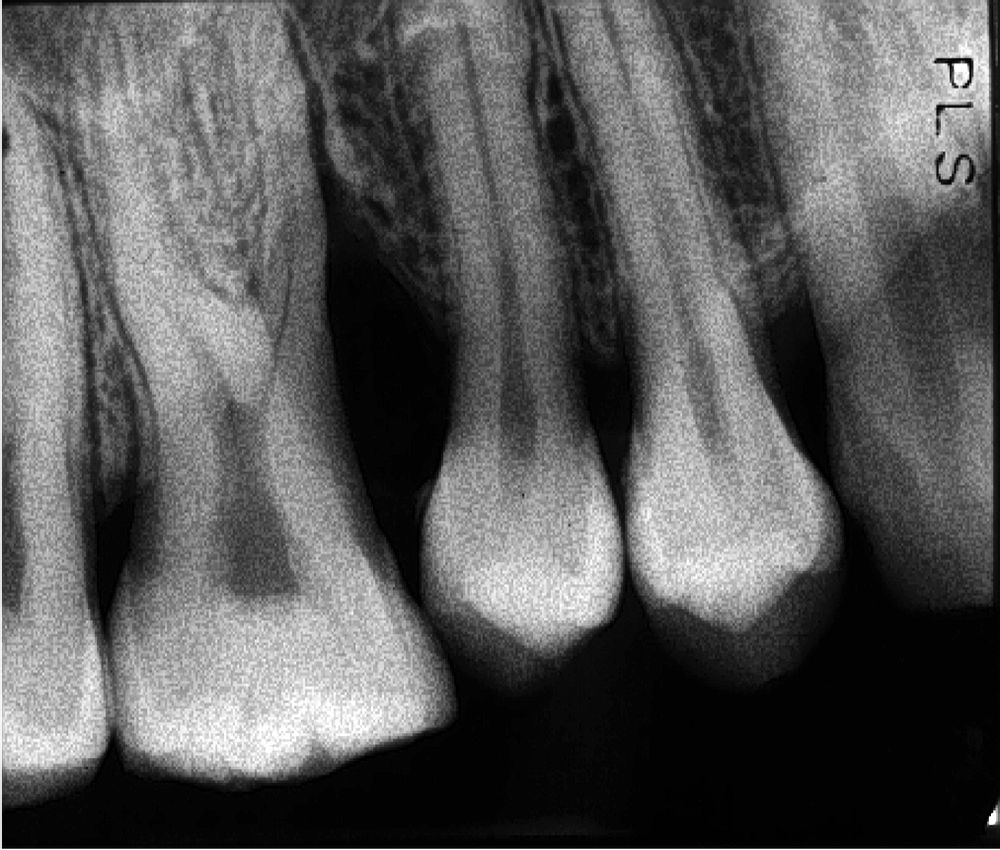

Periapical radiography Pocket Dentistry Intraoral X-Ray Technique The following intraoral radiographs are available:. This chapter summarizes seven basic steps to produce all types of intraoral radiographs: Describe image receptors used to acquire intraoral radiographic. Upon completion of this course, the dental professional should be able to: The patient stabilizes the receptor by biting on a tab or bitewing holder. Two fundamental intraoral techniques can be used independently. Intraoral X-Ray Technique.

Intraoral periapical radiographs. (A) Immediate postoperative Intraoral X-Ray Technique This chapter summarizes seven basic steps to produce all types of intraoral radiographs: The patient stabilizes the receptor by biting on a tab or bitewing holder. Upon completion of this course, the dental professional should be able to: Describe image receptors used to acquire intraoral radiographic. Two fundamental intraoral techniques can be used independently or combined for positioning an image. Intraoral X-Ray Technique.